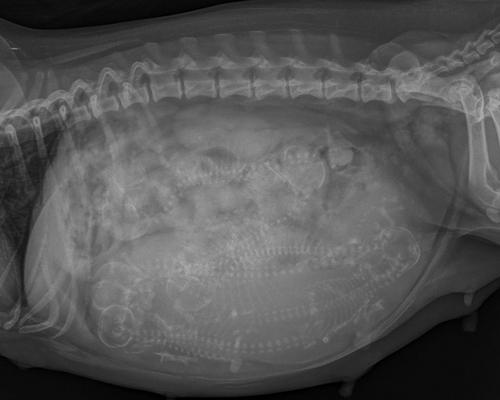

Tiineysröntgenessä käytiin tiineysvuorokaudella 56, jossa eläinlääkäri arvioi olevan kuusi pentua näkyvillä. Samalla Bella sai herpesrokotteen tehosteen ja paino punnittiin. Bellan paino oli 17,9kg eli painokertymä oli 5,5 kg eli 44 % nousua lähtöpainosta. Vatsanympärys oli 76cm. Helena Koskentalon Koirankasvattajan käsikirjassa normaaliksi painon kehitykseksi koko tiineyden aikana kerrotaan 20-55 % nousua pentueen koosta riippuen. Koska pentuja oli tiineysröntgenen perusteella havaittavissa "vain" kuusi, arvioimme pentujen koon olevan melko suuria.